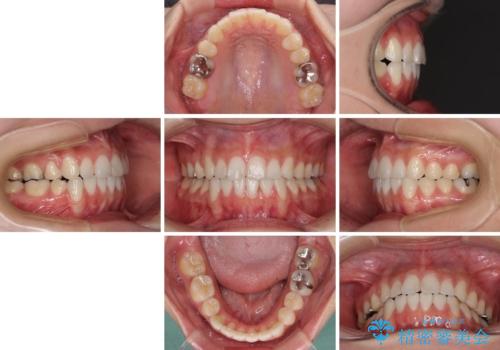

- 上下の八重歯を気にして来院された患者様です。

上下ともに八重歯の後ろの歯を1歯ずつ抜歯し、補助装置(リンガルアーチ)を用いて八重歯の位置を改善し、その後インビザラインにより矯正治療を行うこととしました。

途中海外留学をされたため、治療期間は長くなりましたが、事前に補助装置やワイヤー装置を併用したことで、きれいな歯列に仕上げることができました。